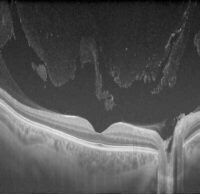

Vitreous Detachment & Floaters

This is a cross section of the posterior part of the eye, taken with a machine called OCT (optical coherence tomography). The retina layers are nicely displayed in shades of grey. The vitreous, which is the fluid in the back part of the eye, is typically clear and represented as black on an OCT. When… Read More